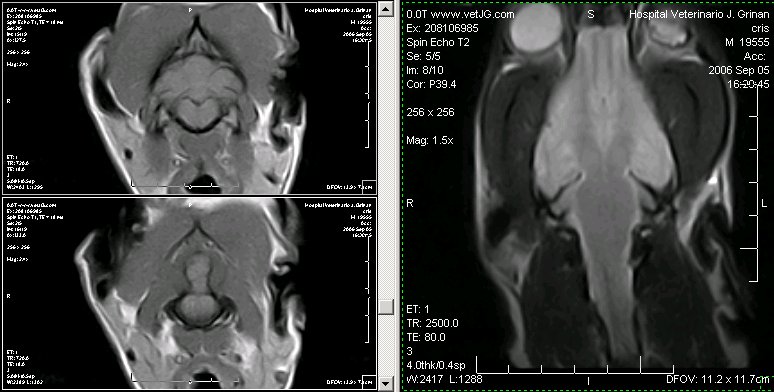

Detalle del mielencéfalo canino en una MRI. Cortes transversales pot. en T1 y corte dorsal pot en T2